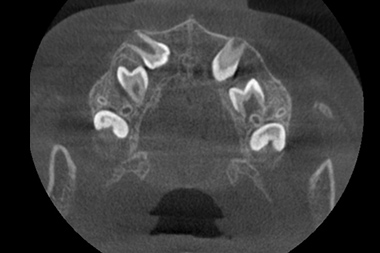

CT検査

3次元情報から、歯の位置・埋伏歯(歯冠の全てまたは一部が顎の骨や歯肉の中に埋まって出ていない歯)・過剰歯(決まった本数よりも多く歯が生えてくること)などを確認します。埋伏歯や過剰歯があると、歯が移動する際に適切な動きができなくなってしまうため、事前に不要な歯を確認しておく必要があります。また歯の移動に大きく関係する骨の厚さや距離などの情報も得られ、精度の高い矯正治療のための重要な情報源を採取することができます。

埋伏歯の位置や方向が確認できる

CT検査の例

CT検査で確認できる軸位断図

CTを使用すると、左記の軸位断図のように様々な角度の断面から歯の位置などの確認をすることができます。

3D構築画像

アキシャル像

コロナル像

サジタル像